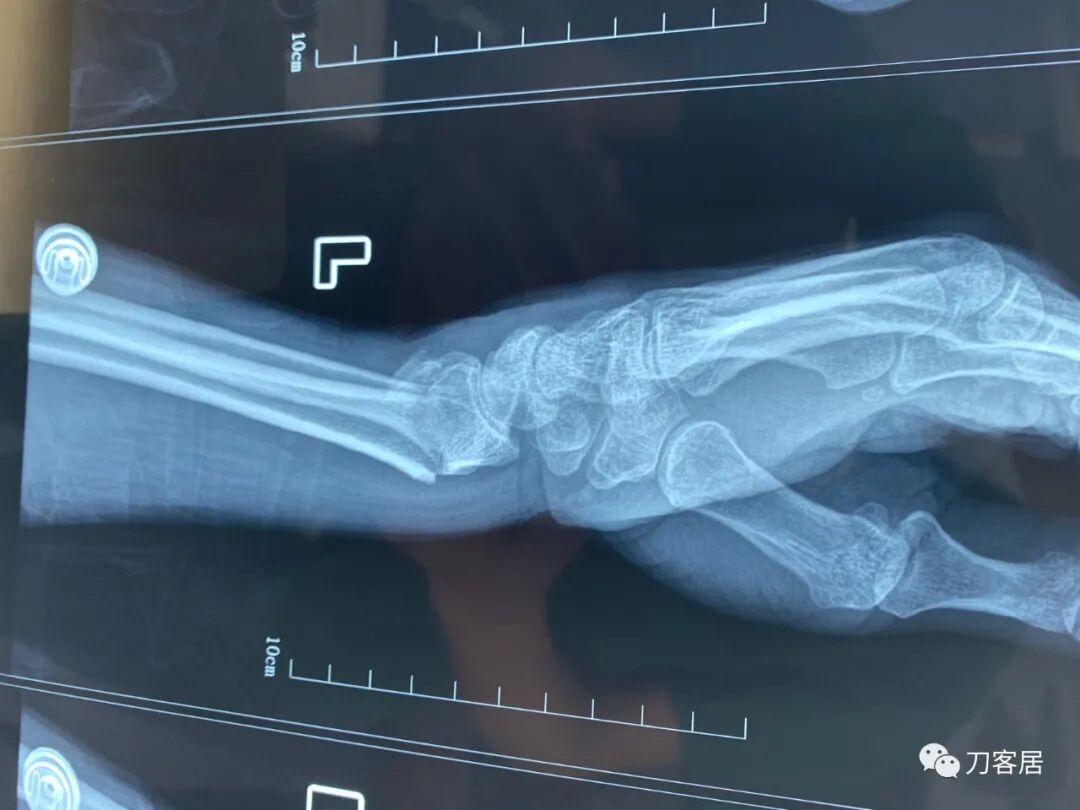

下面是这个6岁孩子,尺桡骨远端双骨折的术前及术后片子和外观照片。

2.  这个骨折处理起来也很简单,单纯的打石膏托或者中医的小夹板,或者正规的包括腕关节和肘关节的管型石膏外固定4周即可治愈该骨折。实在不行,如果这个孩子比较听话,不太调皮的话,用一本书,一个三角巾悬吊固定4周,都可以治愈该骨折。但是给这个患者用外固定架做了手术,而且桡骨远端的几颗克氏针距离骨折线太近,其中一枚克氏针进入到骨折间隙内。从这个术中图片来看,术者的外固定手术技术也有待于进一步的提高。毕竟术者应该还很年轻。从X线片来看,前臂及手的尺侧有不透光影,应该还使用了外固定石膏绷带托,而且我猜测应该是高分子的石膏绷带托,这个是纯属猜测,不一定是对的,不过如何解释前臂尺侧的不透光影呢?如果真是用了石膏绷带外固定的话,那为啥要做手术呢?外固定架术后就不该再用石膏绷带托辅助了。